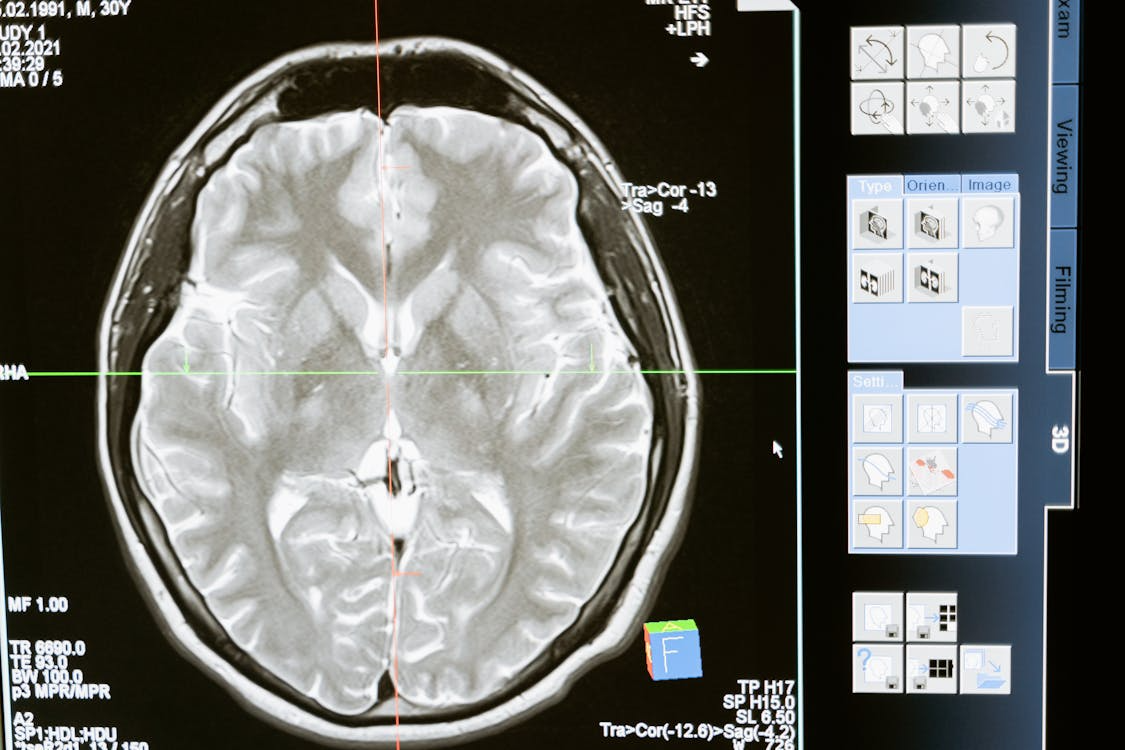

Recent research shows that lithium isn’t just a drug—it’s a trace mineral found naturally in the brain. Scientists have discovered that it may help support memory and overall brain function.

In fact, people with Alzheimer’s disease tend to have lower levels of lithium in key areas of the brain.